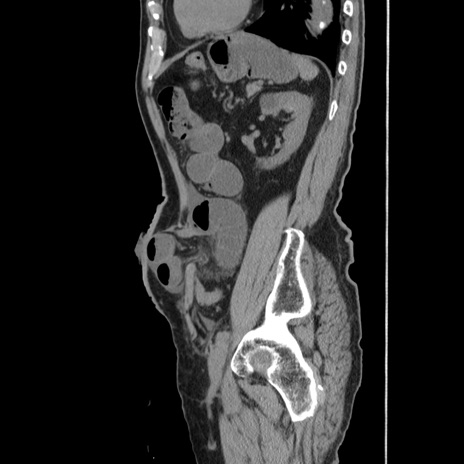

症例24(矢状断像)

【症例】80歳代男性

【主訴】左側腹部痛、嘔吐

【現病歴】本日早朝より左腹部に痛みあり。昼頃嘔吐認めたため、救急要請。

【既往歴】直腸癌(Mile手術)、胆摘

【身体所見】意識清明、BT 35.9℃、BP 221/93mmHg、SpO2 97%(RA) 、腹部:左ストーマ周囲に限局性の腹部膨隆あり。 膨隆部自発痛・圧痛あり・軟。

【データ】WBC 7700、CRP 0.09